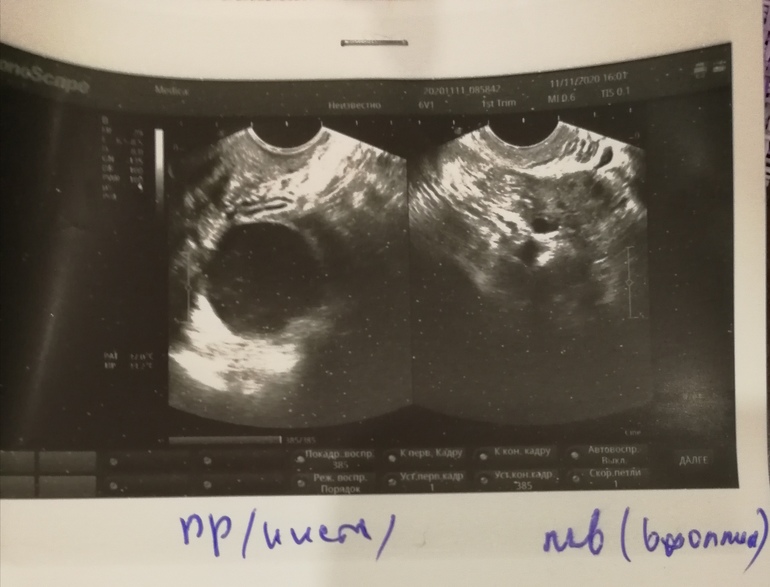

А я на УЗИ сейчас заходить буду. Что то жаба задавила тесты вхолостую переводить, вдруг О не было или эндик 2 мм?! Отпишусь из дома скоро.

Да бля. Хорошо что сходила. Киста справа. Там и труба непроходима. Не поняла какая. Но по фото - фолликулярная. Никакой О слева и близко не было, а я ее так "чувствовала" 😂😂😂Зато эндик 10 мм! Восстановился, слава яйцам. Жду М.

Непроходима по лапаре?

11.11.2020

Да. Устье заросло.

А размер кисты?

35х35 уже